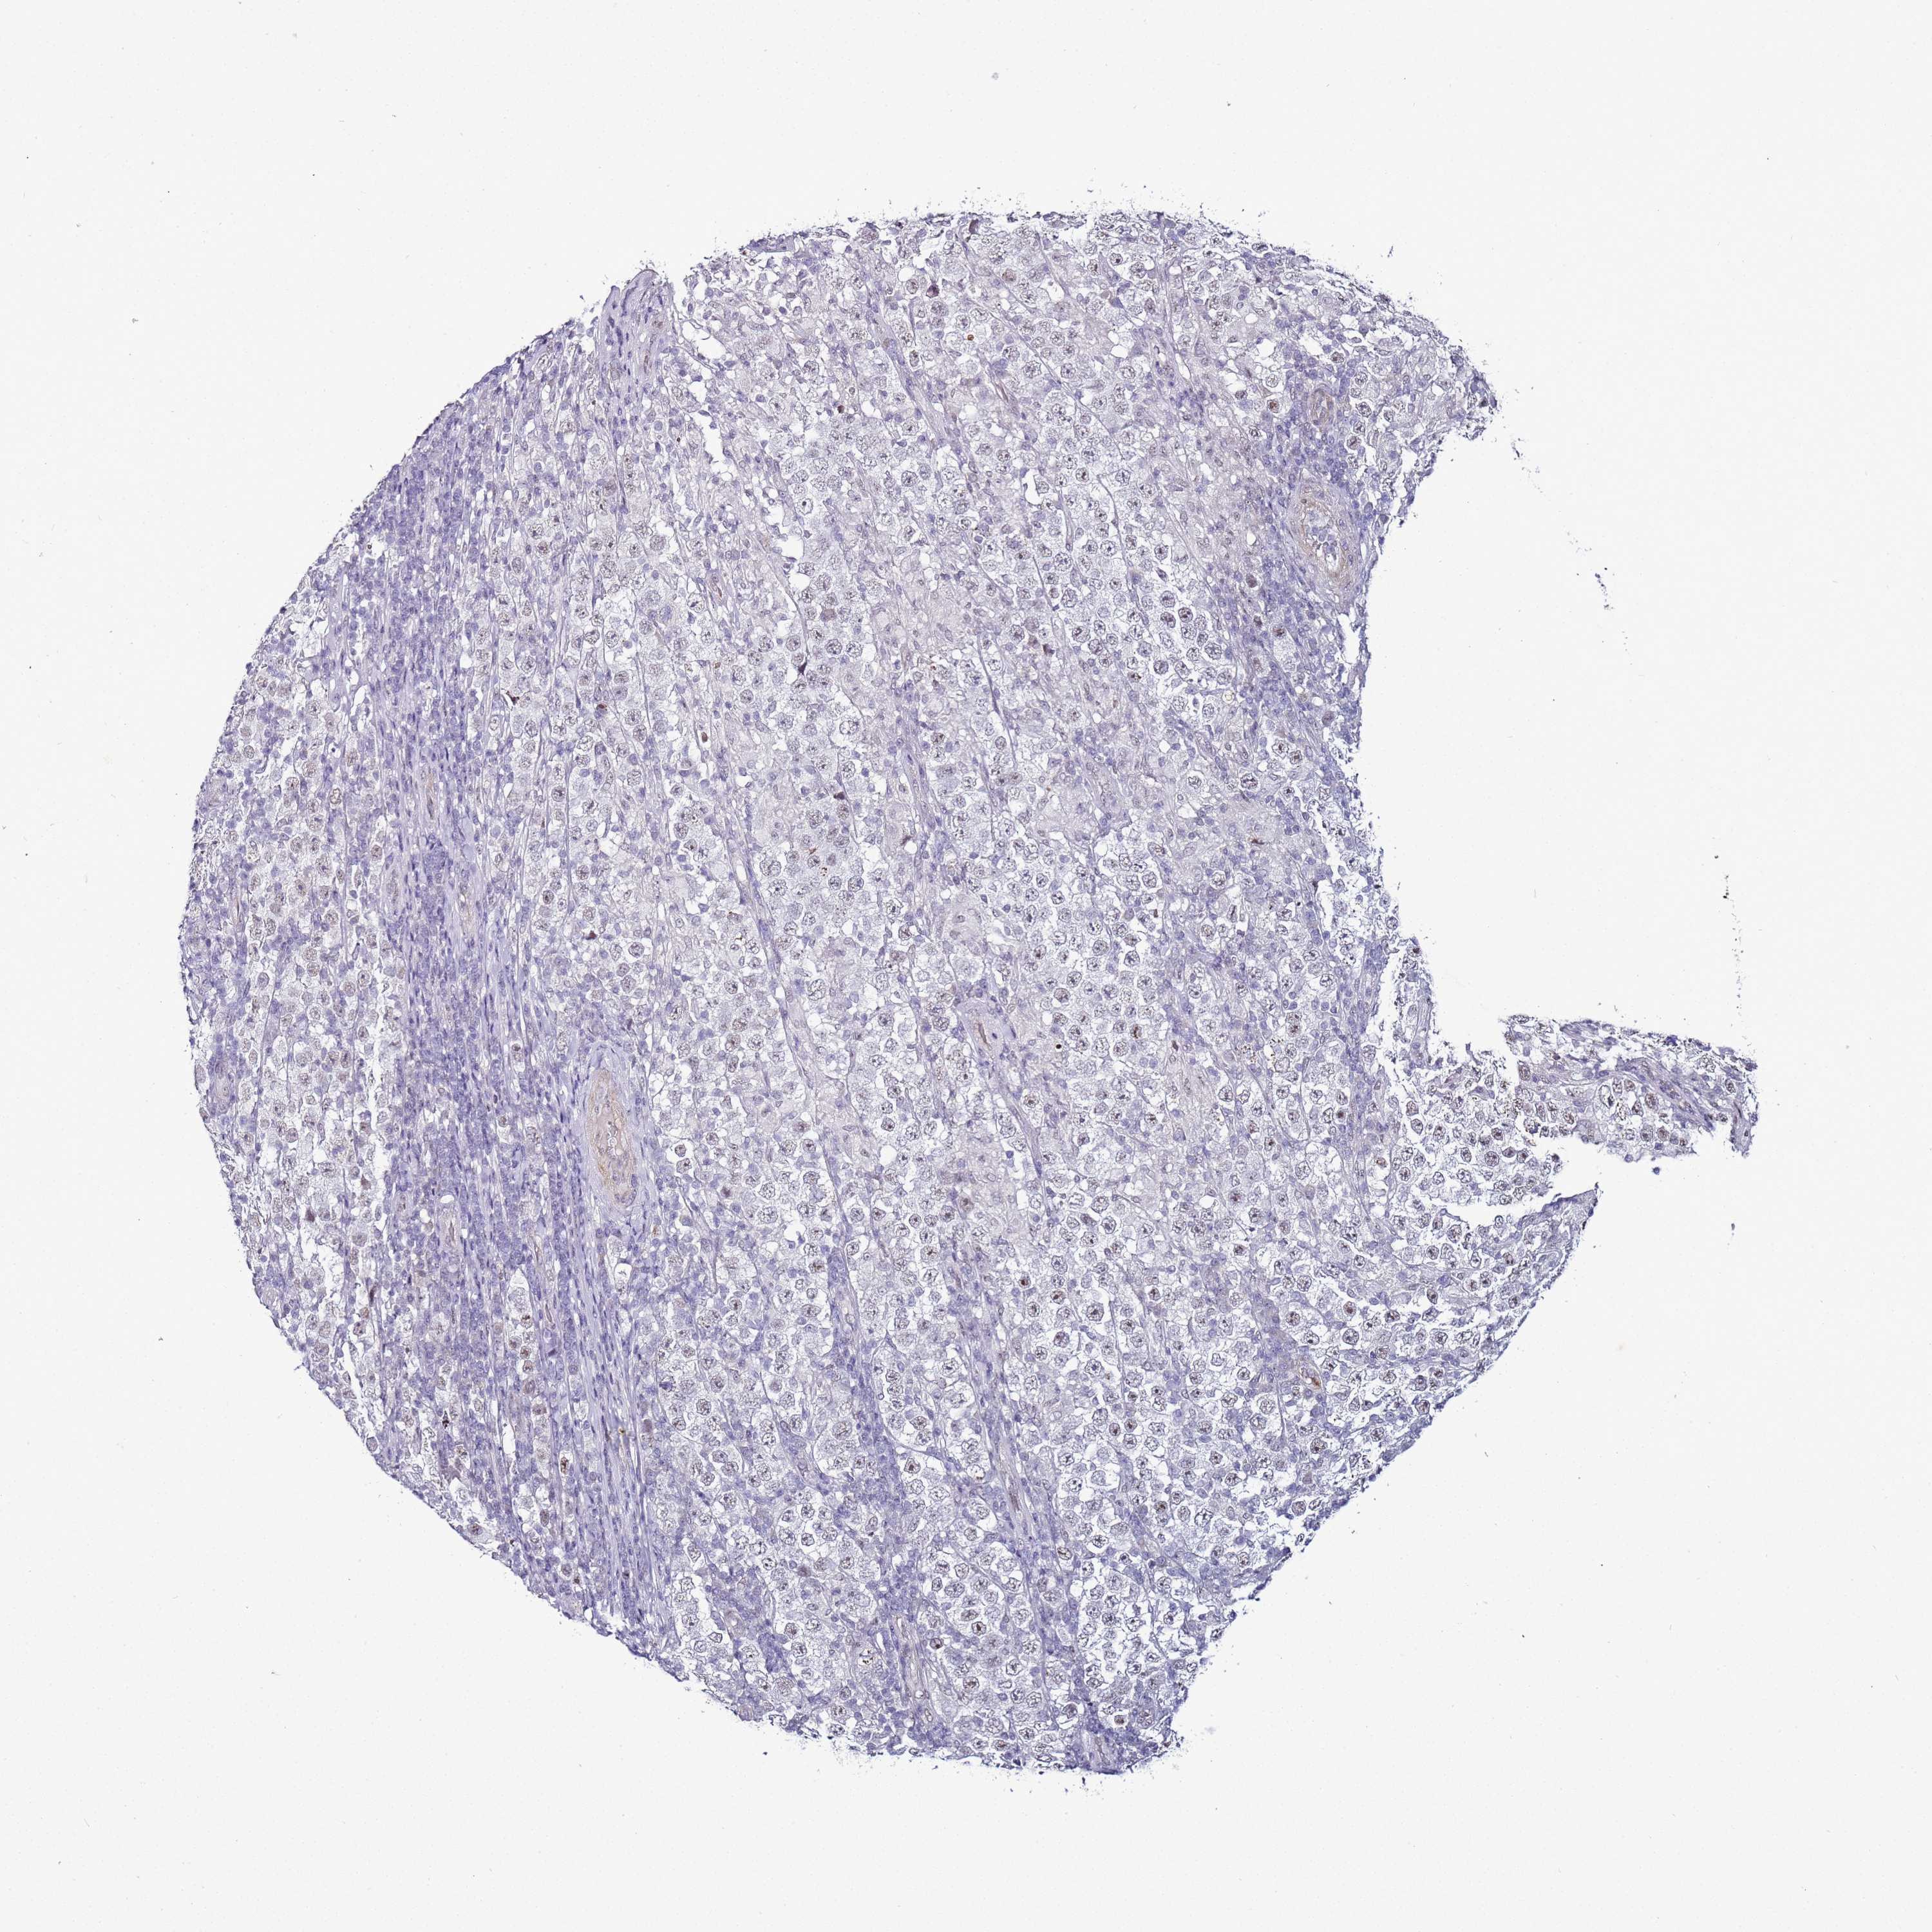

TESTIS CANCER - Protein expressioni

A mouse-over function shows sample information and annotation data. Click on an image to view it in a full screen mode. Samples can be filtered based on level of antibody staining by selecting one or several of the following categories: high, medium, low and not detected. The assay and annotation is described here.

Note that samples used for immunohistochemistry by the Human Protein Atlas do not correspond to samples in the TCGA dataset.

Antibody stainingi

Antibody staining in the annotated cell types in the current human tissue is reported as not detected, low, medium, or high, based on conventional immunohistochemistry profiling in selected tissues. This score is based on the combination of the staining intensity and fraction of stained cells.

Each image is clickable and will lead to virtual microscopy that enables deeper exploration of all samples and also displays staining intensity scores, fraction scores and subcellular localization as well as patient and tissue information for each sample.

Antibody CAB046007

Urothelial carcinoma, High grade

Seminoma, NOS